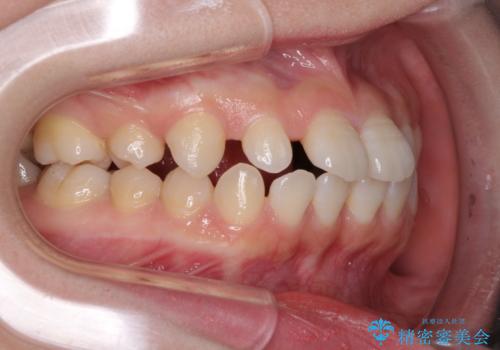

- 歯の欠損による隙間だらけの歯並びを気にして来院された患者様です。

上顎左右1本ずつ欠損していたため、歯列矯正により欠損部位にスペースを集め、その後欠損部位をインプラントにて補綴することとしました。